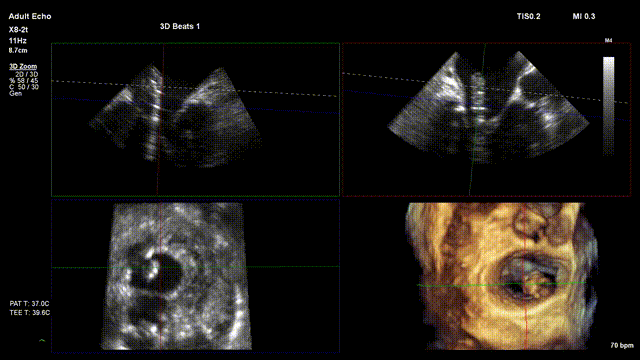

术前超声评估:

术前TTE超声提示二尖瓣大量反流

术中超声

手术在单纯超声引导下完成,采用左侧第六肋间微创切口心尖入路,在食道探头引导下,清晰识别MitraFix®输送系统准确跨瓣,超声科骆志玲主任、朱达主任通过Multivue在三维超声引导下精准定位瓣膜方位,在X-plane下精准定位瓣膜释放高度及保证系统的同轴性,最终将人工瓣膜准确释放于二尖瓣瓣环。